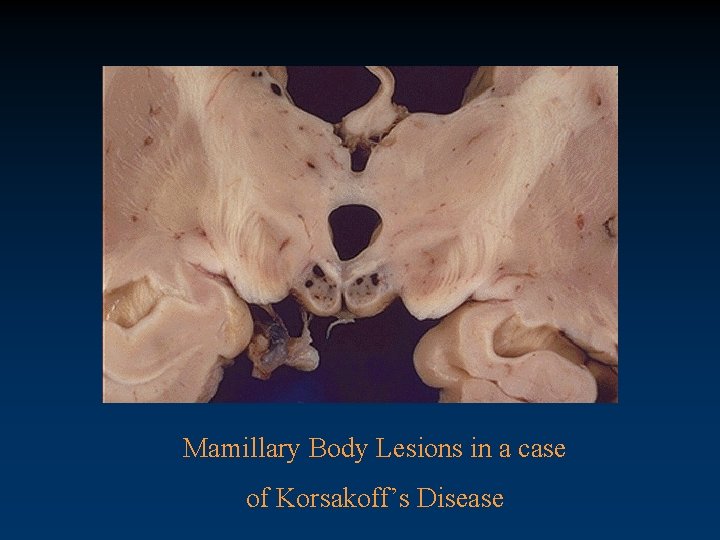

Diencephalic Syndromes • Korsakoff Syndrome associated with ETOH abuse or malabsorption – prominent encoding deficits – role of frontal pathology • Vascular disease • Thalamic trauma

Mamillary Body Lesions in a case of Korsakoff’s Disease